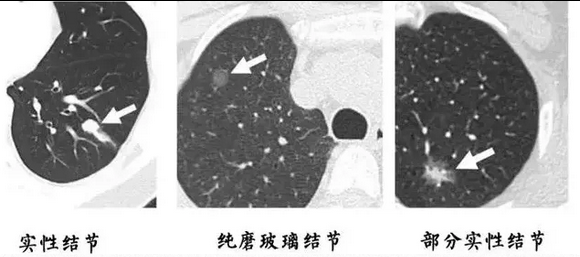

在肺部CT检查中,医生经常提到“磨玻璃结节(GGO)”和“实性结节”,很多患者一听到这些术语就紧张起来,甚至有人认为“磨玻璃结节比实性结节更危险”或“实性结节才是真的肺癌”,那么事实究竟如何呢?

磨玻璃结节和实性结节本质上只是影像学上的表现,两者各自有不同的临床意义。磨玻璃结节指的是在CT上呈现半透明、模糊状的结节,可能与肺泡结构的轻度改变有关。大多数磨玻璃结节是良性的,如炎症后遗留的纤维化,但部分持续存在或增大的磨玻璃结节可能是早期肺癌(特别是原位腺癌或微浸润腺癌)。不过,这类癌症通常生长缓慢,恶性程度较低,患者的生存率极高,因此并不意味着磨玻璃结节就一定“很糟糕”。

而实性结节则表现为边界清晰、密度较高,可以是良性病变(如钙化灶、炎症结节等),也可能是恶性肿瘤。一般来说,如果实性结节较大、形态不规则、边缘毛刺状或伴有血管增粗等特征,恶性肿瘤的可能性增加。

因此,无论是磨玻璃结节还是实性结节,都不能单凭影像就断定其性质。医生通常会根据结节的大小、形态、增长速度以及患者的病史来判断是否需要进一步检查或随访。对于小而稳定的磨玻璃结节,通常建议定期随访,而对于可疑的实性结节,可能需要穿刺活检或手术治疗。